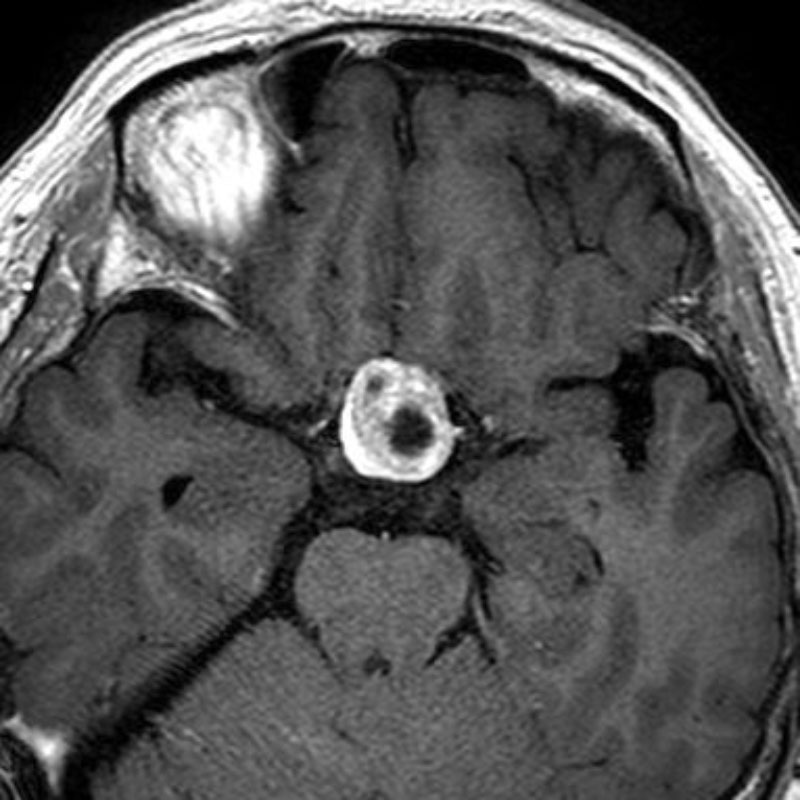

520

'24年3月

40代

小脳上衣腫

頭蓋内腫瘍摘出術

No.’24_22 手術前1

No.’24_22 手術前2